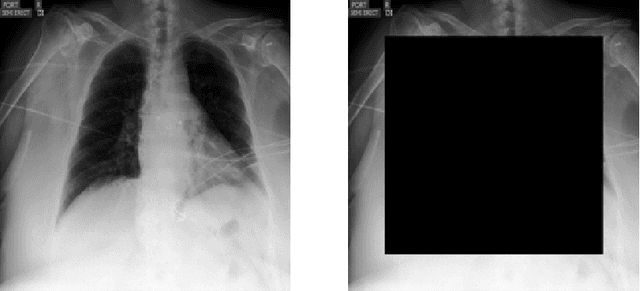

Abstract:Deep predictive models often make use of spurious correlations between the label and the covariates that differ between training and test distributions. In many classification tasks, spurious correlations are induced by a changing relationship between the label and some nuisance variables correlated with the covariates. For example, in classifying animals in natural images, the background, which is the nuisance, can predict the type of animal. This nuisance-label relationship does not always hold. We formalize a family of distributions that only differ in the nuisance-label relationship and introduce a distribution where this relationship is broken called the nuisance-randomized distribution. We introduce a set of predictive models built from the nuisance-randomized distribution with representations, that when conditioned on, do not correlate the label and the nuisance. For models in this set, we lower bound the performance for any member of the family with the mutual information between the representation and the label under the nuisance-randomized distribution. To build predictive models that maximize the performance lower bound, we develop Nuisance-Randomized Distillation (NURD). We evaluate NURD on a synthetic example, colored-MNIST, and classifying chest X-rays. When using non-lung patches as the nuisance in classifying chest X-rays, NURD produces models that predict pneumonia under strong spurious correlations.

Abstract:Early results in using convolutional neural networks (CNNs) on x-rays to diagnose disease have been promising, but it has not yet been shown that models trained on x-rays from one hospital or one group of hospitals will work equally well at different hospitals. Before these tools are used for computer-aided diagnosis in real-world clinical settings, we must verify their ability to generalize across a variety of hospital systems. A cross-sectional design was used to train and evaluate pneumonia screening CNNs on 158,323 chest x-rays from NIH (n=112,120 from 30,805 patients), Mount Sinai (42,396 from 12,904 patients), and Indiana (n=3,807 from 3,683 patients). In 3 / 5 natural comparisons, performance on chest x-rays from outside hospitals was significantly lower than on held-out x-rays from the original hospital systems. CNNs were able to detect where an x-ray was acquired (hospital system, hospital department) with extremely high accuracy and calibrate predictions accordingly. The performance of CNNs in diagnosing diseases on x-rays may reflect not only their ability to identify disease-specific imaging findings on x-rays, but also their ability to exploit confounding information. Estimates of CNN performance based on test data from hospital systems used for model training may overstate their likely real-world performance.